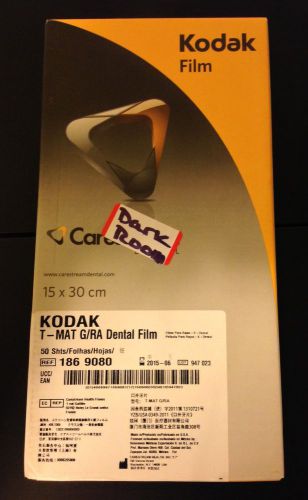

1 Pack New Sealed Kodak T-Mat G/RA Dental Film 50pack 15X30cm 06/2015 NEW